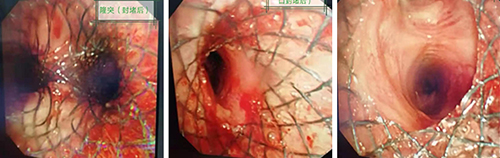

行气管镜检查,镜下见:左主支气管起始部瘘口形成,侵及隆突及气管远端,瘘口大于1.5cm,管腔部分狭窄,常规的气管支架已无法解决患者面临的问题。

治疗前(镜下)

镜下瘘口封堵后